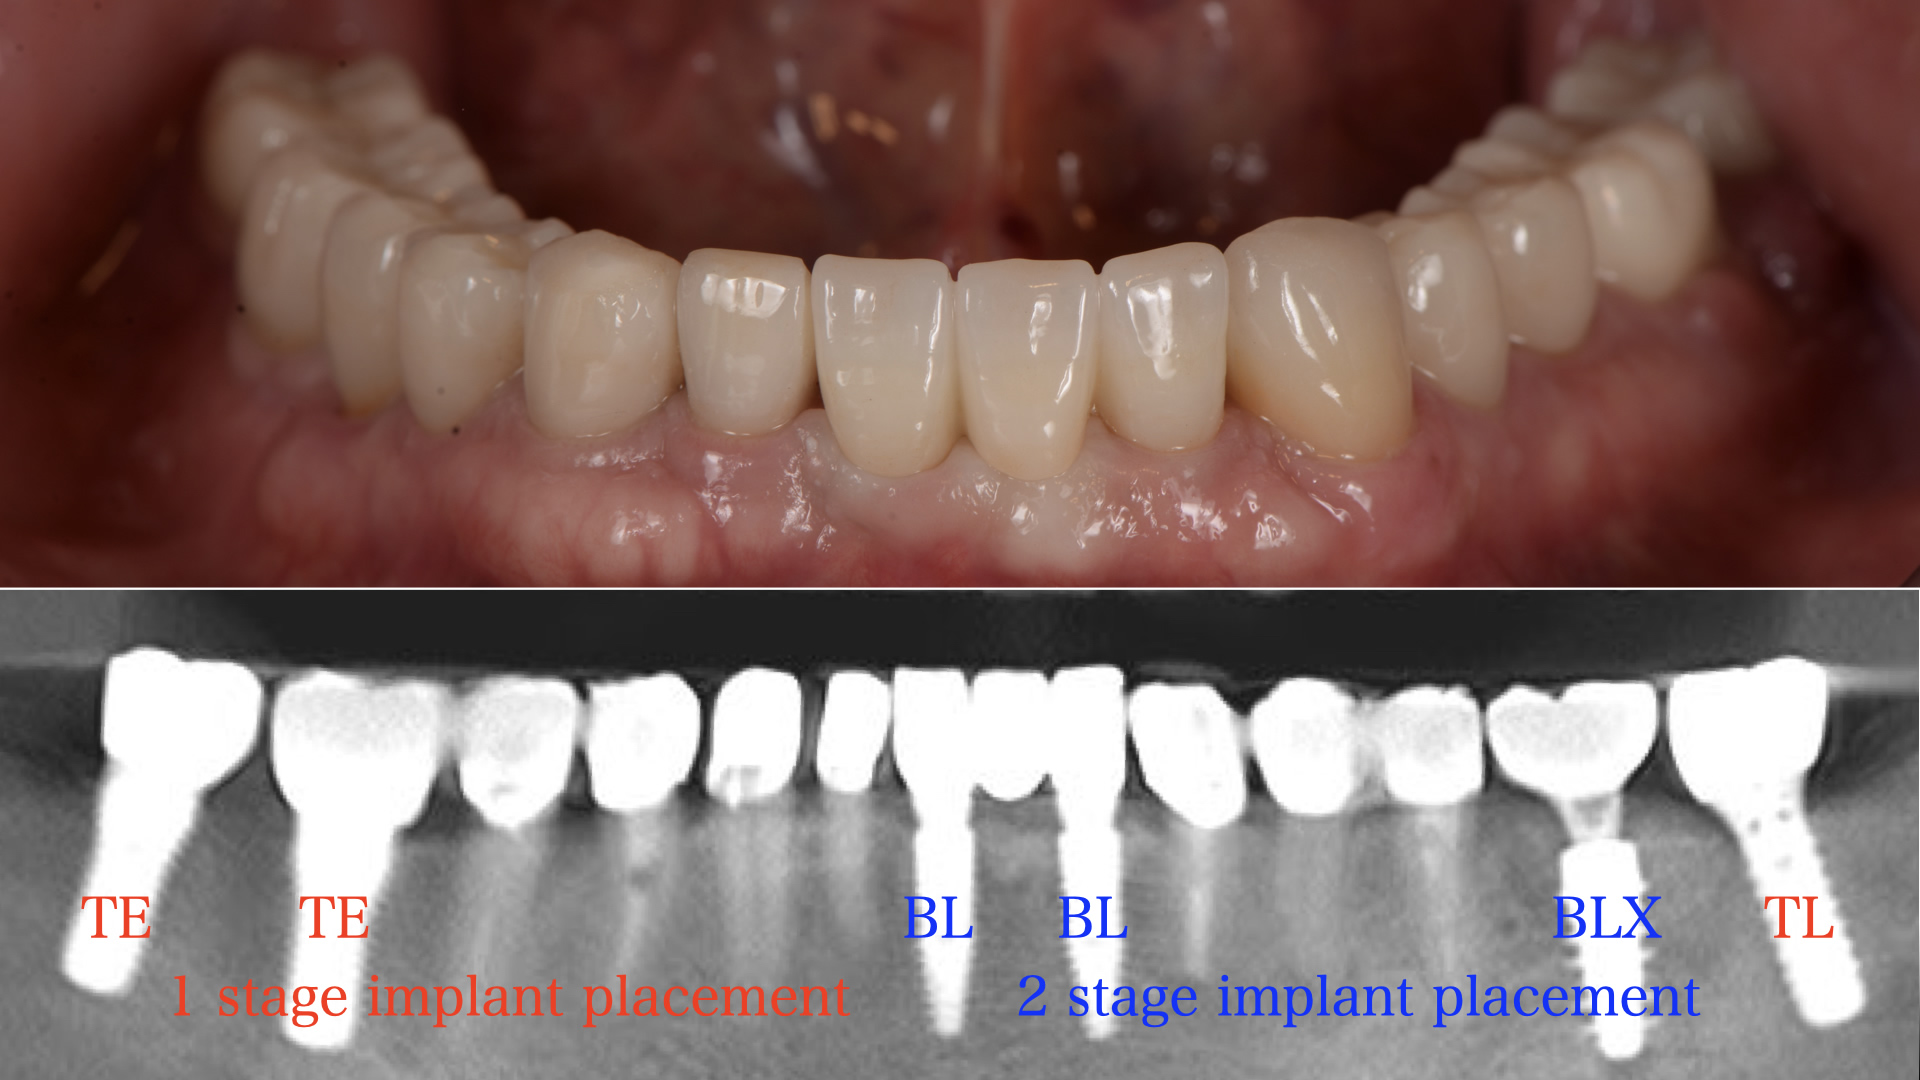

インプラント治療による一例。(赤文字青文字部)インプラント治療は、『よく噛める機能性』『天然歯に近い審美性』『舌の感触などの快適性』に今現在最も優れた治療方法である。インプラント治療は、事前の骨の状態や神経、動脈の走行位置などを十分に把握して行わなければ、大量出血、感覚麻痺、その他様々なリスクを伴う。また、噛み合わせを考慮した位置に正確に埋め込まなければ、歯としての機能を与えることが困難となり、ただの飾りとなってしまう。

(図説)フィクスチャーが骨と結合した後に、粘膜貫通部からアバットメントと上部構造が装着された一例。

(骨の状態や粘膜の厚みによっては、必ずしもこのように審美的に仕上がるとは限りません)